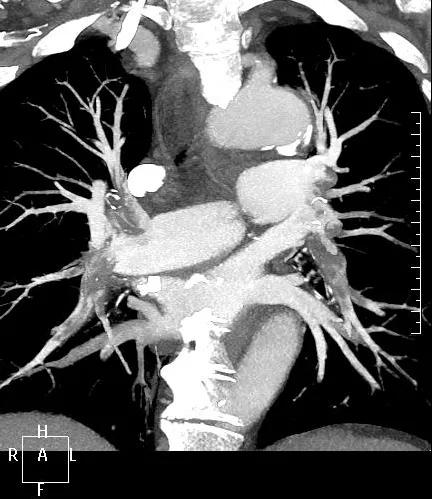

近日,一名港胞翁阿姨在我市突發(fā)急性肺栓塞,生命垂危。市二院在接到120出車指令后,迅速響應(yīng),患者入院后開通綠色通道,經(jīng)急診科、心內(nèi)科、介入科、重癥醫(yī)學(xué)科等多學(xué)科專家開展聯(lián)合會診,并于當晚9點行“下腔靜脈、肺動脈造影+導(dǎo)管溶栓+濾器植入術(shù)”,患者終于轉(zhuǎn)危為安,經(jīng)后續(xù)治療與精心護理,病情逐漸穩(wěn)定,現(xiàn)已轉(zhuǎn)入普通病房。